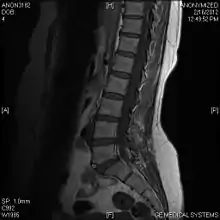

Limbus vertebra

A limbus vertebra is a bone tubercle formed by bone trauma on a vertebral body, bearing a radiographic similarity to a vertebral fracture. The anterior-superior corner of a single vertebra is the common site for this defect although it can also be seen at the inferior corner as well as the posterior or anterior margin. Anatomically, it is assumed to be an intra-vertebral body herniation of the disc material occurring during adolescent growth spurt when the ring apophysis has not yet fused. It was first described by Schmorl in 1927[1] and later in detail by Leif Sward and Adad Baranto.

Viewed in a lateral radiograph, it appears as a triangular shaped bone fragment, not unlike an anterior lip fracture, but with softer edges.

Limbus vertebra is not always symptomatic, but severe cases may lead to more serious pathological conditions and chronic pain. In rare instances, a posterior limbus vertebra has been described causing radiculopathy due to nerve root compression. [2]